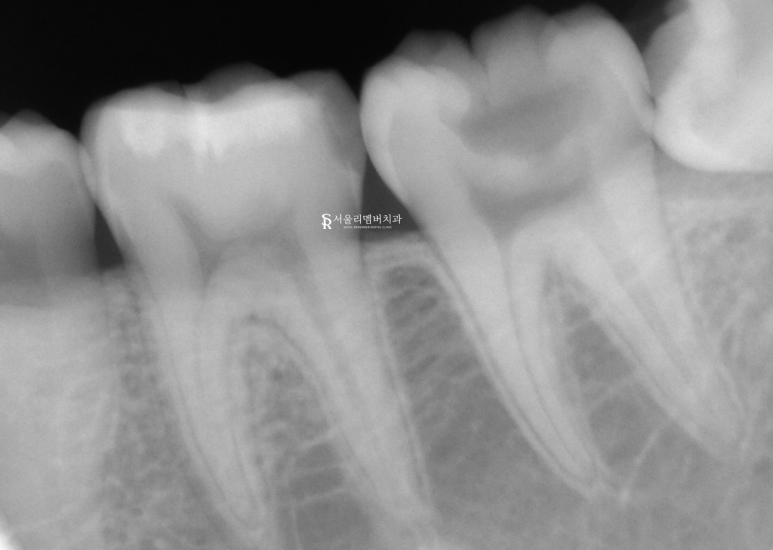

상악은 양호한 편이였는데요.

그러나 하악은 그렇지 않았습니다.

표면이 깨져 있는 파절과

심한 충치들이 곳곳에 생겨 있었죠.

치아 주름인 groove(구)를 따라

검게 물들어 있는 우식이 관찰되었는데요.

특히 왼쪽 오른쪽 두 번째 큰 어금니

37번이 심각했습니다.

꽤 크게 파절이 나타나

표면이 탈락되어 있었으며

그 주변으로 충치들이 생겨 있는 모습이네요.

이렇게 파절이 관찰되는 곳은

깨진 틈 사이로 세균이 침투하여

내부 조직이 감염되었을 확률이 높습니다.

역시나 예상이 틀리지 않았네요.

치수 부근에도 병소가 퍼져 있었습니다.